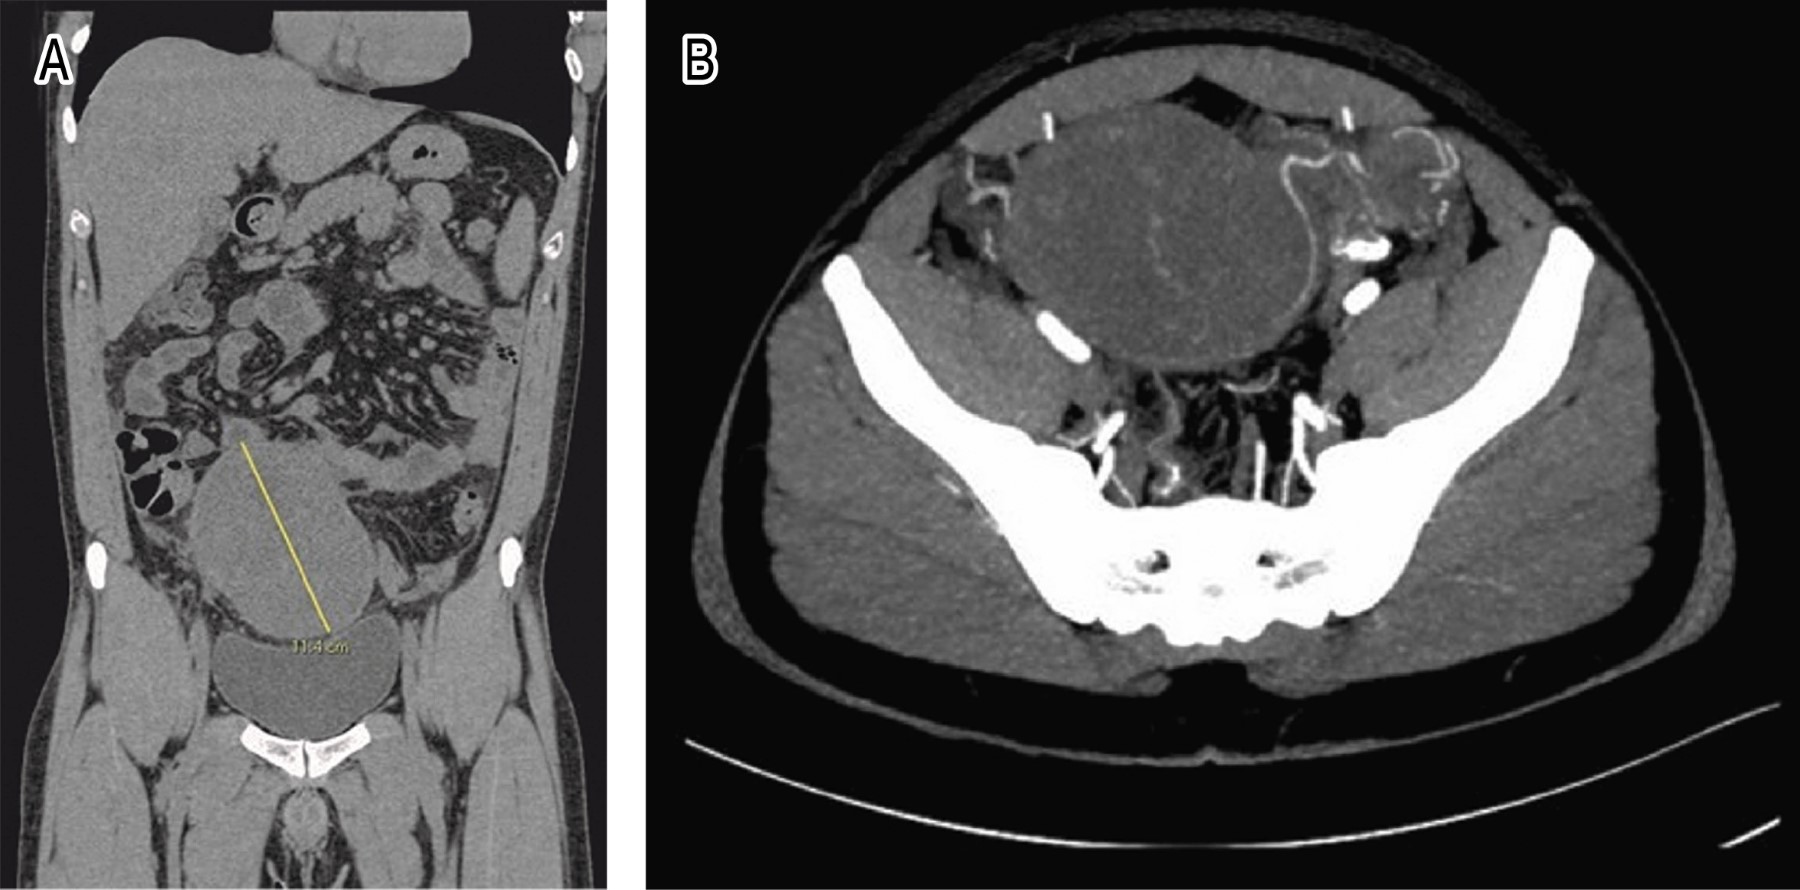

Incidental intraabdominal seminoma

Cryptorchidism is considered one of the main risk factors for the formation of germ cell tumors and is associated with the generation of seminomas. The indicated treatment is orchidopexy for children under two years of age and orchiectomy for postpubertal subjects, with their respective follow-ups. Germ cell tumors represent 1% of malignant tumors in men; their etiology is unknown, although several hypotheses seek to elucidate it, while their diagnosis requires a complete clinical history; however, there are several cases diagnosed incidentally. We describe the case of a patient with a history of orchiectomy at three days of life due to cryptorchidism, who arrives at the emergency room with abdominal pain for several days, with acute appendicitis as the first differential diagnosis; however, he cannot receive a complete etiological diagnosis given his condition and its evolution, so we performed a diagnostic laparoscopy where incidentally finding an intra-abdominal seminoma with successful surgical intervention. This case highlights the importance of investigating whether patients with a history of testicular surgery have received follow-up or not to identify the probable etiology of the condition presented.

Figure 1

Figure 2